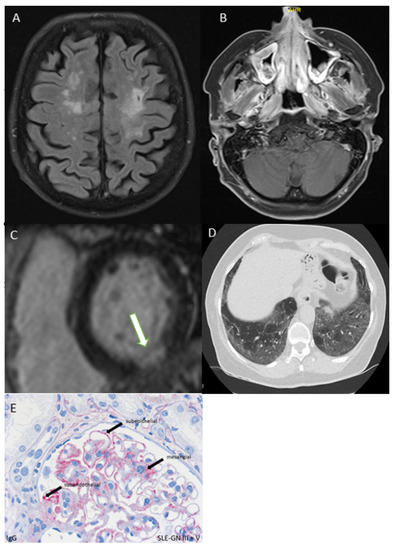

3.5.2. CNS or PNS Involvement